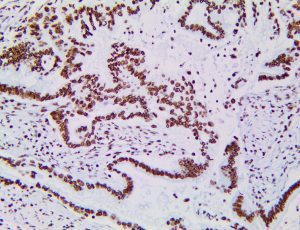

The first cytokines released are interleukin 1β (IL-1β) and tumor necrosis factor-α (TNF-α), which attract a variety of circulating white blood cells (WBCs) to the infection site, including neutrophils, monocytes, macrophages, and natural killer (NK) cells. This response, along with the antipathogenic chemicals released by these cells (i.e., complement), comprise the innate immune response. These cells directly attack the invading pathogen and also release additional cytokines, chief among them interleukin-1 and 6 (IL-6). IL-6 is essential for invoking the adaptive immune response, which calls T-cells, B-cells, and T helper (Th) cells to the infection site. IL-6 also stimulates further recruitment, proliferation and activation of macrophages.

It is the ICU physician who is most likely to witness one of the deadliest manifestations of the abnormal immunological response, the cytokine storm syndrome (CSS). This response is also referred to by some as the cytokine release syndrome (CRS). CSS is characterized by continuous activation and expansion of macrophage and lymphocyte populations, which secrete large amounts of cytokines, causing the cytokine storm. This massive cytokine release is akin to hemophagocytic lymphohistiocytosis (HLH) disease, a syndrome characterized by initial unchecked and persistent activation of cytotoxic T lymphocytes and NK cells.